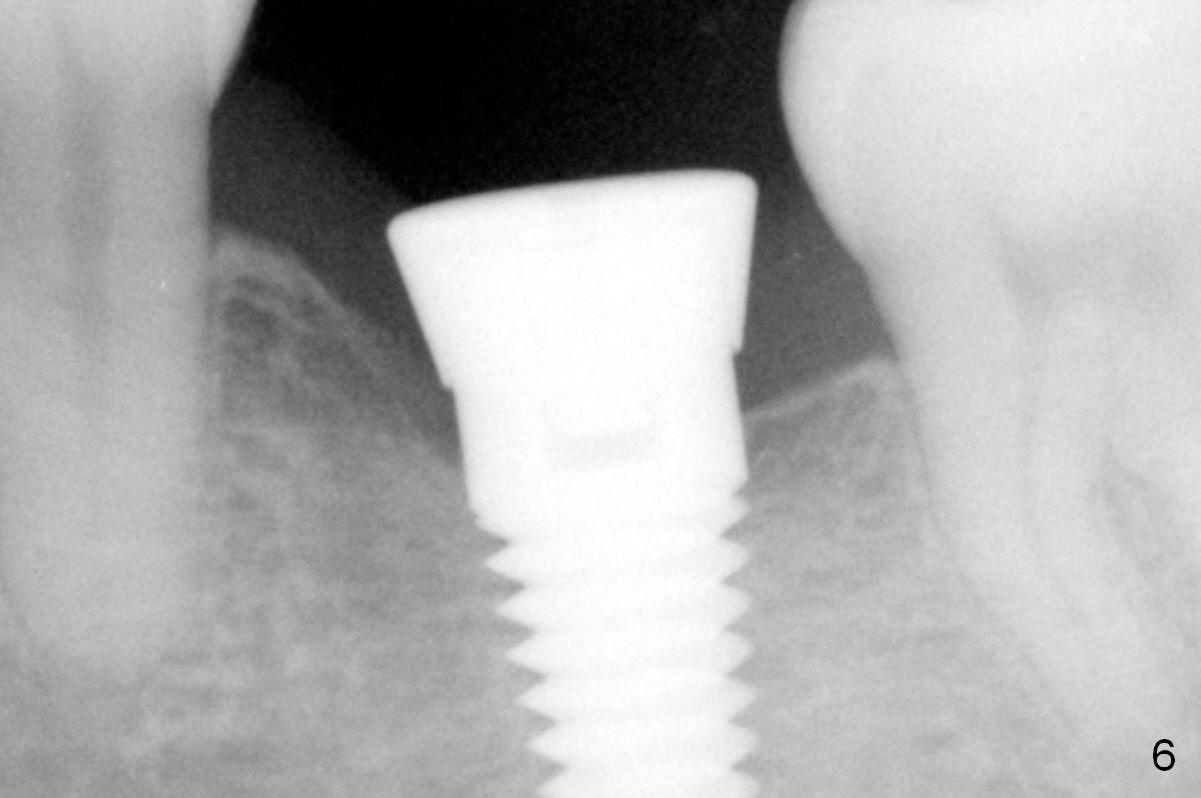

The mesial and distal crests of the tooth #19 were even for a 50-year-old man 7 years ago. Three years later, swelling developed around the distal root with bone loss (Fig.2 *). Three months later, localized swelling occurred (Fig.3 *) with oozing. The patient had thrombopenia (platelet 40 K). The tooth was extracted with suture. There is distolingual root tip resorption. Two months and a half later (Fig.4), a 6x17 mm implant was placed (Fig.5). The implant osteointegrated 5 months postop (Fig.6). The distal crest re-appears 5 months (Fig.7), 2 years (Fig.8) and 2 years 8 months (Fig.10) post cementation. At the last appointment, the patient complained of pain and swelling at #30 with mesial bone loss (Fig.10 *), as compared to Fig.9 taken 9 years ago. The mesiolingual pocket is deep. After scaling and Chlorhexidine irrigation, Arestin is locally administered.